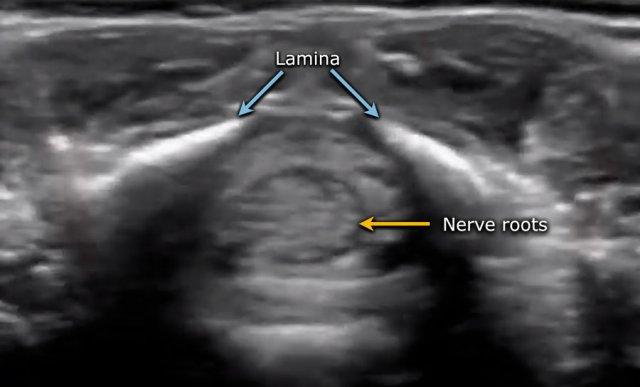

Hình ảnh cắt ngang vùng đuôi ngựa.

Đuôi ngựa được quan sát như một bó các sợi di động.

Nếu trẻ nằm ở tư thế nghiêng, các sợi sẽ lắng xuống phía sau theo trọng lực.

Nếu trẻ được khảo sát ở tư thế nằm sấp với gối kê dưới bụng, các sợi sẽ di chuyển về phía bụng.

Luôn luôn thu nhận hình ảnh trên mặt phẳng cắt ngang.

Sự di động của các rễ thần kinh được quan sát rõ hơn trên mặt phẳng ngang so với mặt phẳng đứng dọc, đồng thời dễ dàng hơn trong việc đánh giá bệnh lý trong ống sống như filum terminale dày.

Ghi hình ở tư thế nằm nghiêng phải.

Các rễ thần kinh tập trung ở phía phụ thuộc trọng lực nhưng di động tự do.

Khi các rễ thần kinh không di động tự do, đây có thể là dấu hiệu của OSD.